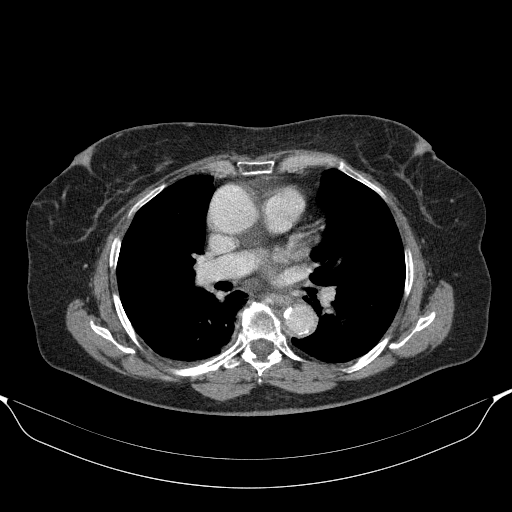

Original VENOUS CT scan

No window - Raw intensity values

Lung window (WL -600, WW 1500 β†’ Low βˆ’1350, High +150)

Mediastinum window (WL 40, WW 400 β†’ Low βˆ’160, High +240)